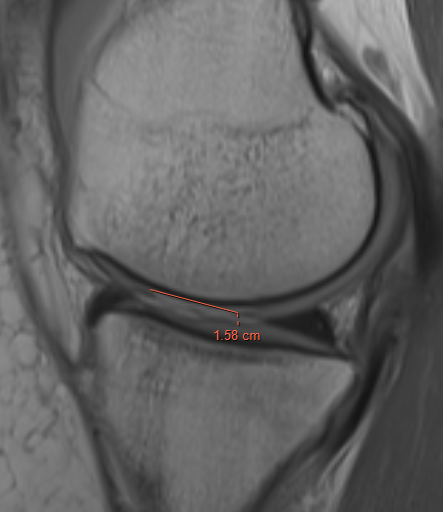

Grade 2: Partial thickness defect < 1.5 cm in diameter

Grade 3: Fissuring to subchondral bone, > 1.5 cm in diameter

Sizing

3 or 5mm graduated probe

- measure in 2 dimensions

- give a size in cm2

- assumes that lesions are basically rectangular

- tend to overestimate size arthroscopically